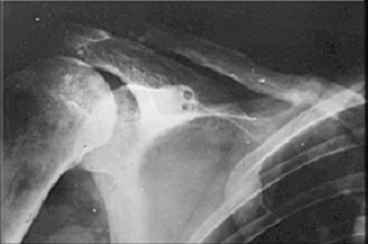

Идеальным вариантом представляется резекция ложного сустава, замещение образовашегося дефекта васкуляризированным малоберцовым трансплантатом и интрамедуллярный блокированный остеосинтез.

В условиях российской бедности мы делали свободным "столбиком" из малоберцовой и неблокированным штифтом. Результат был хороший (фото).